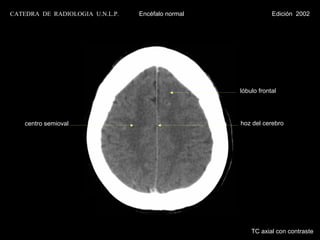

hoz del cerebro

lóbulo frontal

centro semioval

lóbulo parietal

TC axial con contraste